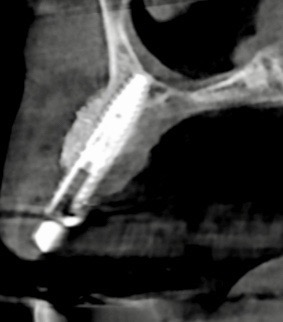

下記の症例は骨幅が薄く、このままでは長期的に安定したインプラント治療が不可能だったので、抜歯と同時に骨造成(GBR)を行い、その後歯肉移植(FGG)を行い、術後安定した経過を辿るよう配慮致しました。